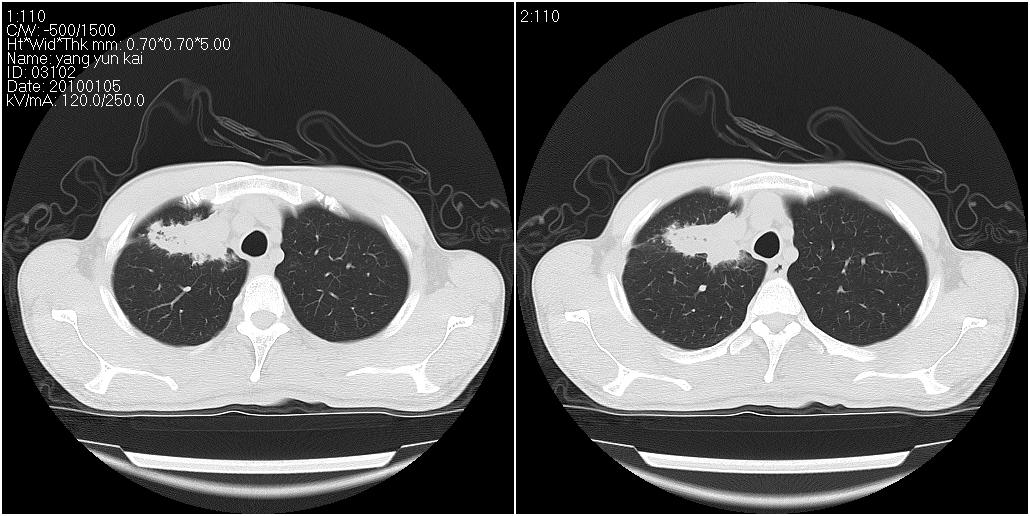

标题: CT23980:男性,47岁。近来咳痰、咳血,血沉增快(40左右),

男性,47岁。近来咳痰、咳血,血沉增快(40左右),痰中未检出结核杆菌。

两肺继发性肺结核并多发性结核球形成,部分病灶内空洞形成。